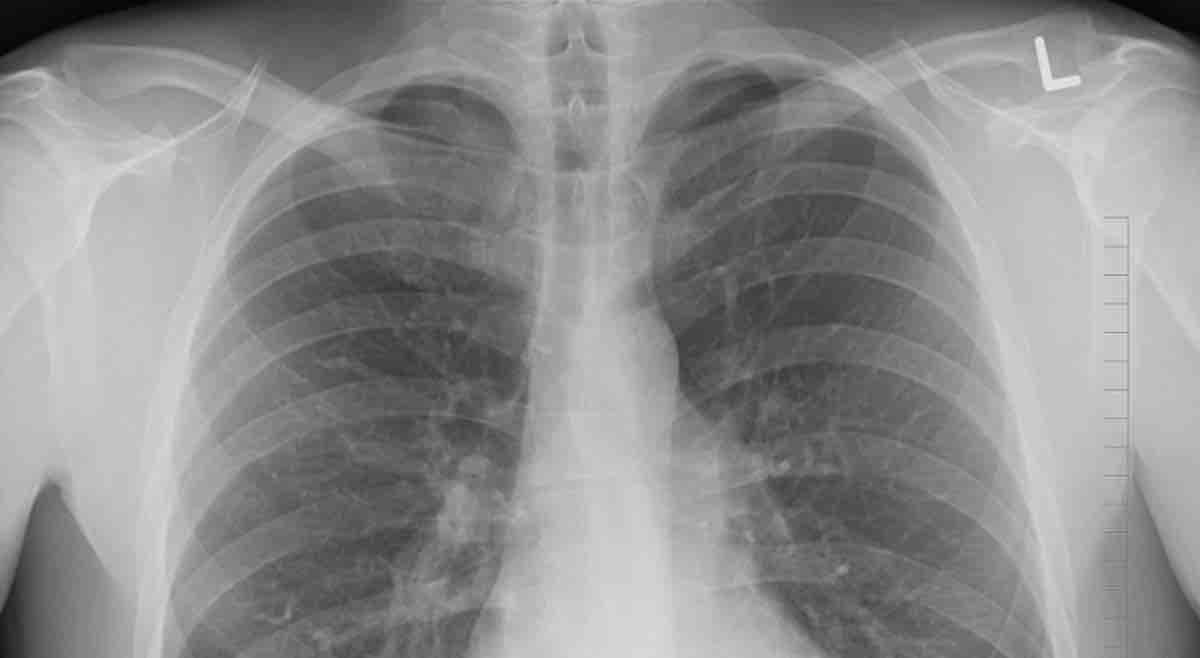

Even in the midst of a global pandemic, it’s important not to forget other infectious diseases, like malaria and tuberculosis, which still require diligent efforts to combat in regions like Southeast and Central Asia, Africa, and Oceania.